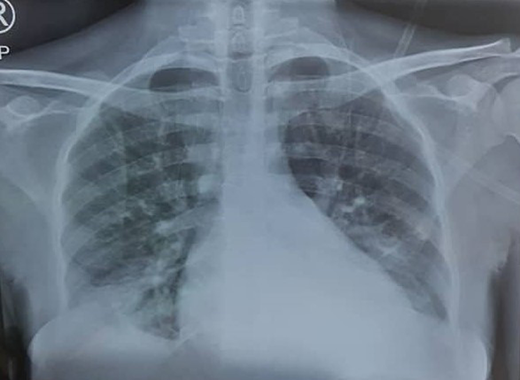

Chest radiograph (PA view) showing pulmonary infiltrates classic to ACS.

A 33-year-old woman with hemoglobin SS (HbSS) in her first pregnancy presented with a cough, severe knee pain, bilateral lower-limb pain, and severe oligohydramnios (reduced amniotic fluid volume) at 34 weeks' gestation. On examination, she was dehydrated. Her temperature was normal, with a pulse rate of 100/min, a respiratory rate of 22/min, and an oxygen saturation (SpO2) level of 88% in room air. She was admitted, received a chest x-ray with abdominal shielding, and administered oxygen with a rebreathable mask. A complete blood count showed an Hb level of 5.5 g/dl and a white cell count of 22 × 106/mL, with neutrophilia of 81%.

The patient's chest x-ray showed radiopacities (Figure 1). Despite an increase in the oxygen flow rate, the twice-daily administration of 1 g of ceftriaxone, and a simple transfusion of 3 units of packed RBCs (PRBCs) within 24 hours, her Hb level only increased to 6.2 g/d, and she remained oxygen dependent. She subsequently had a manual exchange blood transfusion (EBT) with 6 units of ABO Rh D-compatible HbS-negative PRBCs that were less than 7 days old as per the unit protocol. Her postexchange Hb concentration was 8.6 g/dL, and her HbS fraction was 22.3%.

ACS, an important complication of SCD, is characterized by fever and/or respiratory symptoms and a new pulmonary infiltrate on chest x-ray. It is a significant cause of mortality and is frequently seen in pregnant women, with 4 out of 5 deaths in a series of 71 Hb SS women with 177 pregnancies.7 ACS caused nearly 87% of the maternal deaths in a multicenter case series in Ghana.17